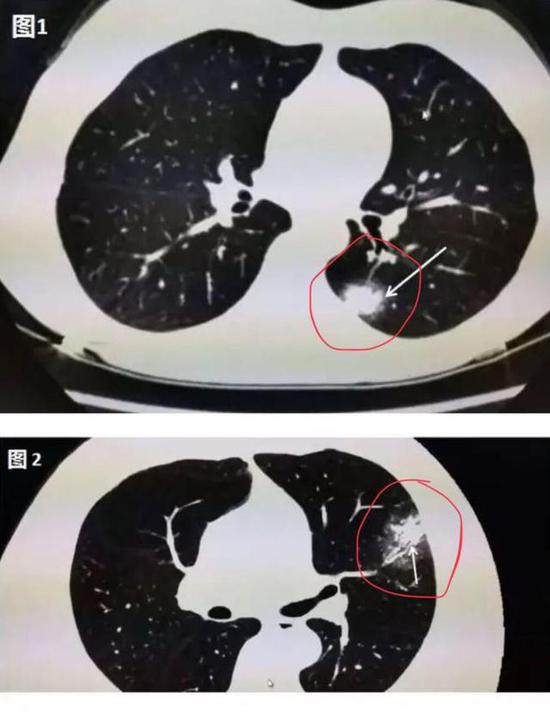

下圖是新冠肺炎患者在做肺部CT時的圖像,肉眼可見的紅色圈內或白色箭頭所指區域,相較于肺部其他正常部位出現了像云霧狀磨砂玻璃一樣的“病灶”,醫學上美其名曰“磨玻璃影”。

▲新冠肺炎患者肺部CT顯示磨玻璃影(圖片來自網絡)

其實,在疾病早期,肺部CT上可能并不會首先出現磨玻璃影。華中科技大學同濟醫學院附屬同濟醫院放射科管漢雄教授發文稱,患者一旦出現咳嗽、持續發熱、不明原因乏力時,CT常常會有陽性發現。肺部CT上可能出現一白色不規則的小斑片(如圖1箭頭所指區域),即“實變結節影”,或者是中央實變、周圍磨玻璃(如圖2箭頭所指區域),也就是中央區域是一白色不規則的小斑片,周圍則像云霧狀磨砂玻璃一樣。隨著病毒的持續“攻擊”,病情發展,感染加重,白色的實變結節區域開始吸收,如同一顆糖融化了一樣,慢慢變為磨玻璃影。

▲圖1:肺部CT上出現一白色的小斑片;圖2:中央區域是一白色的小斑片,周圍則像云霧狀磨砂玻璃一樣(圖片來自網絡)